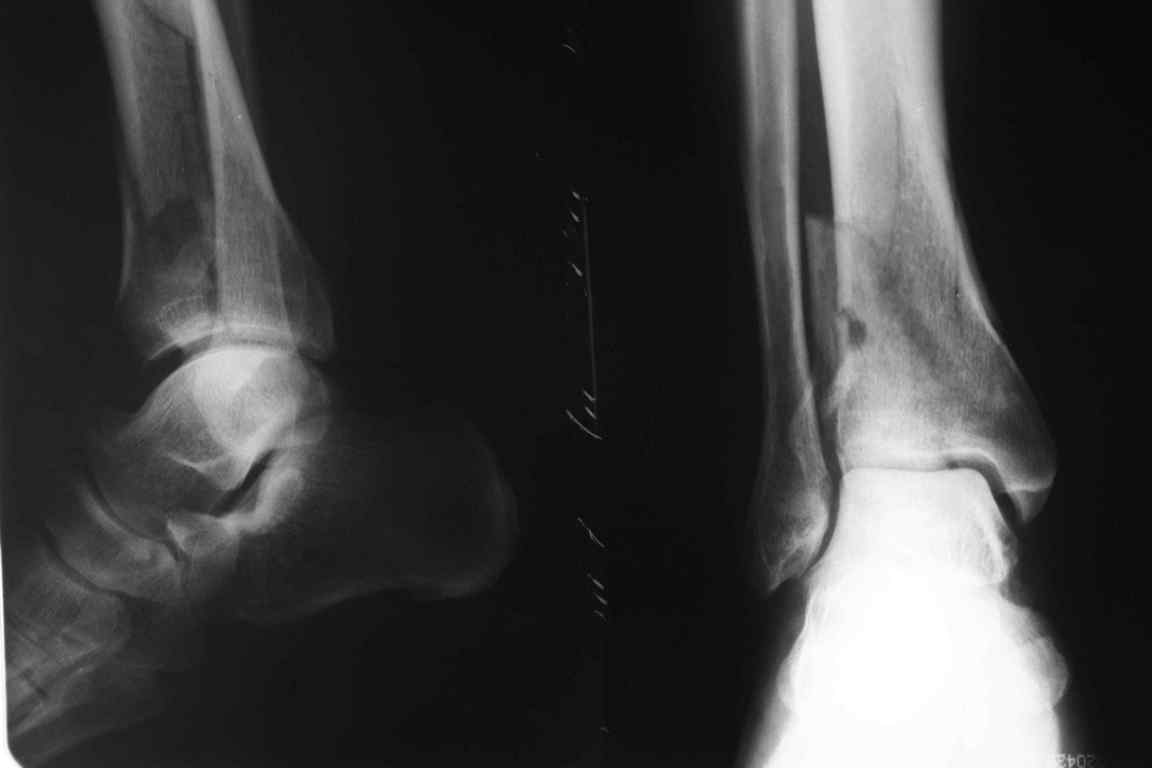

В приложении метафизарный перелом у ребёнка 14лет, с распространением линии перелома на зону роста.

В примере показан не перелом пилона, а эпифизеолиз, м/берцовую кость сознательно не фиксировал(длина её восстановлена, ротации нет),у детей стараемся минимизировать операц.травму, несколько позже разрешил полную нагрузку на ногу(4 недели). Но принцип фиксации б/берцовой кости м.б. таким же.